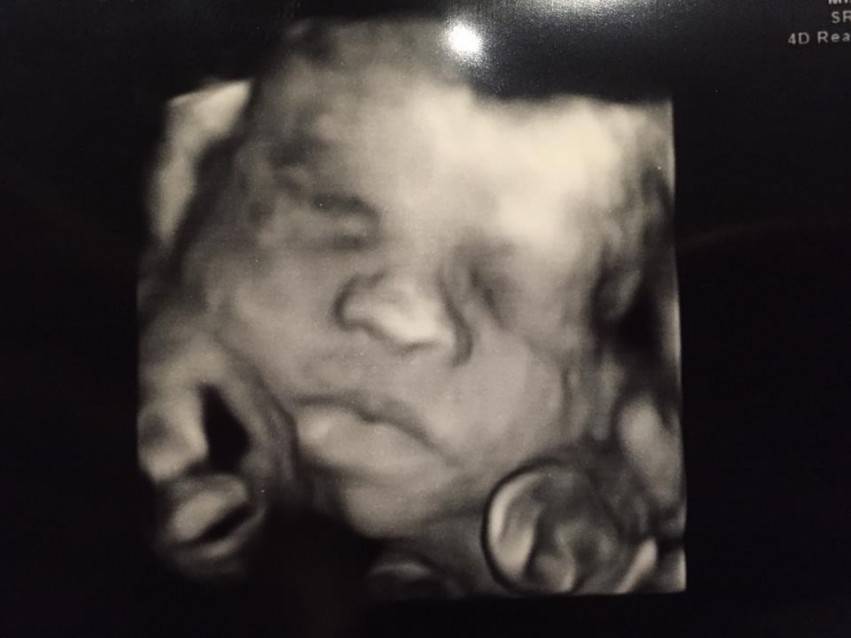

Aleye Meyer è una ragazza di 21 anni in attesa del suo primo figlio. Durante un controllo prenatale presso il suo medico, le immagini dell’ecografia del figlio hanno mostrato qualcosa di unico: un’immagine di Gesù sulla croce. In realtà Aley non si è subito accorta della strana immagine, ma solo dopo una settimana quando un amico glielo ha fatto notare, come racconta lei stessa nel video che segue.

“Abbiamo scattato una foto dell’ecografia con il cellulare per avere una vista più da vicino e dettagliata. Si possono vedere i capelli e le gambe incrociate“, ha raccontato Aley a 14 News.

Ad Aley piace pensare che l’immagine sia un messaggio dall’alto: “Ho preso molte medicine per la malattia di Chron di cui soffro e sono stato molto preoccupata quindi mi sento come se fosse un segno che tutto andrà ok con lui“.

Easton, questo il nome del bambino, è atteso per giugno. Noi facciamo tanti auguri a questa neomamma e voi? Che ne pensate di questa immagine?